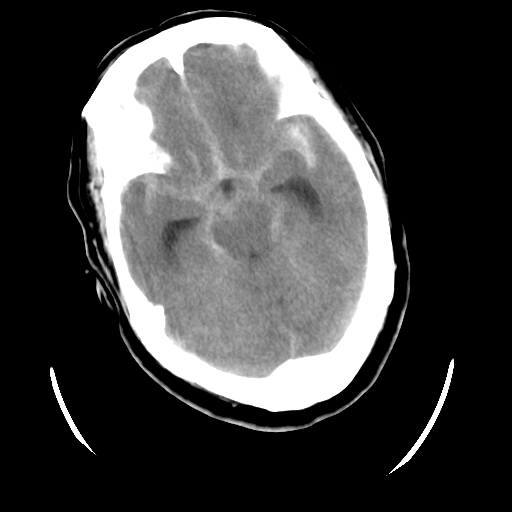

以下是引用随光逐影在2009-4-11 0:07:00的发言:[br]12天前ct检查:1)蛛网膜下腔出血。2)脑室系统少量积血。3)脑积水。[br]今日ct检查:1)多发性脑梗塞,伴部分梗塞区脑皮质渗血。2)脑积水。[br]